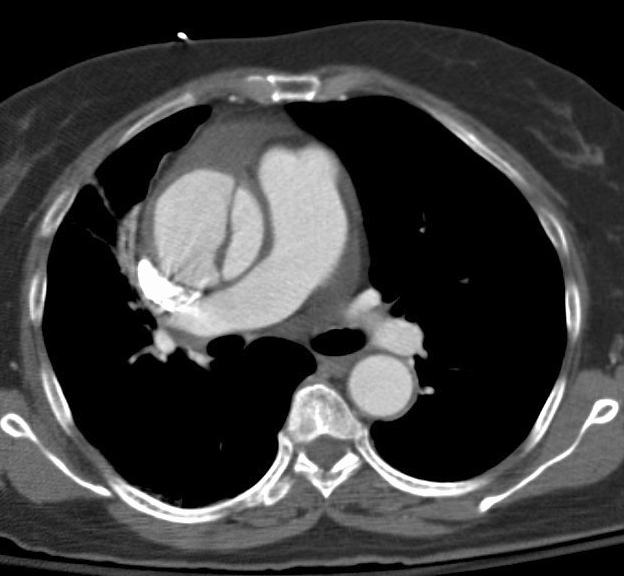

Ao diss 4c

Date: 12/31/2004